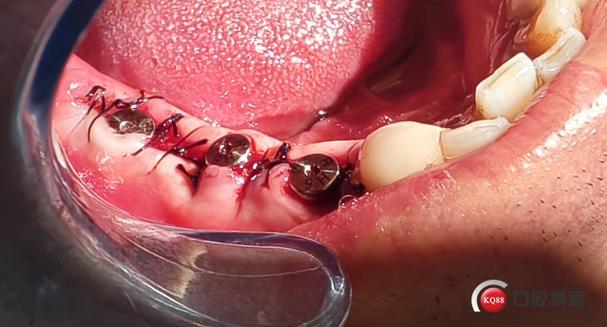

| 拔牙与窝洞预备 | 微创拔除患牙,尽量保存牙槽骨壁;根据种植体直径扩大拔牙窝,去除炎性组织。 | 手术当天 |

| 种植体植入 | 将经过表面处理的钛合金种植体植入拔牙窝,确保初期稳定性>35Ncm(必要时植骨)。 | 拔牙后立即 |

| 缝合与术后处理 | 无张力缝合牙龈,放置胶原蛋白海绵促进愈合;拍摄X线片确认种植体位置。 | 手术结束即刻 |